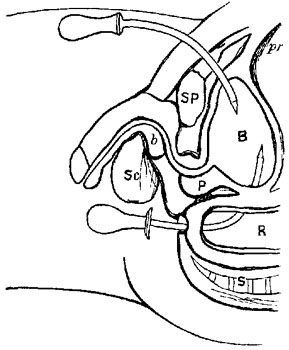

Ligature above Omohyoid.—Using the anterior border of the sterno-mastoid as a guide, but leaving it gradually above to a little nearer the mesial line, an incision (Plate IV. fig. 1), varying in length according to the depth of fat and cellular tissue in the neck, but with its central point opposite the upper border of the cricoid cartilage, must be made through skin, platysma, and superficial fascia. While making the incision the head should be held back, and the face slightly turned to the opposite side; the parts being now relaxed by position, the edges of the wound must be held apart by blunt hooks or copper spatulæ, and the deep fascia carefully divided over the vessel, which will be recognised by the pulsation. It may be noted here that even in thin subjects the sterno-mastoid edge invariably overlaps the vessel, though in many anatomical diagrams it would appear to be in part subcutaneous.

The sheath of the vessel is then to be cautiously opened to the extent of about half an inch. The internal jugular vein, possibly much distended, may overlap the artery on its outer side, and will require to be pressed, emptied, and held out of the way. A small portion of the artery being thoroughly separated from the sheath, the aneurism-needle must be passed from without inwards to avoid the vein, and keep as close to the artery as possible to avoid the vagus.

Ligature of Carotid below the Omohyoid.—An incision in precisely the same direction as the former, but at a slightly lower level, is required, but the dissection is rather more difficult. The edge of the sterno-mastoid when exposed must be drawn outwards; the sterno-hyoid and thyroid inwards; the omohyoid upwards; the sheath opened, and the descendens noni or its branches drawn to the tracheal side. The jugular vein and vagus are both at the outer side, and must be avoided, while the inferior thyroid artery and sympathetic nerve both lie behind the vessel, and may be included in the ligature if care be not taken.

Varieties.—Sedillot's Operation.—To secure the artery still lower in the neck: An incision two and a half inches long, from the inner end of the clavicle obliquely upwards and outwards in the interval between the sternal and clavicular attachments of the sterno-mastoid; this divides the superficial textures; the two portions of muscle must then be drawn apart. The internal jugular vein lies in the interval, and must be drawn to the outside before the artery can be seen at all, and it is this that makes this operation very difficult and dangerous, especially on the left side, where the vein is close to the artery, and probably even crossing it from left to right. The thoracic duct is behind.

Malgaigne's modification of the above is an improvement: to expose the external attachment of the muscle, to cut it through and turn it to the outside, as in the operation for ligature of the innominate, then to divide or pull inwards sterno-hyoid and sterno-thyroid, thus exposing the sheath. The needle must be passed from without inwards.